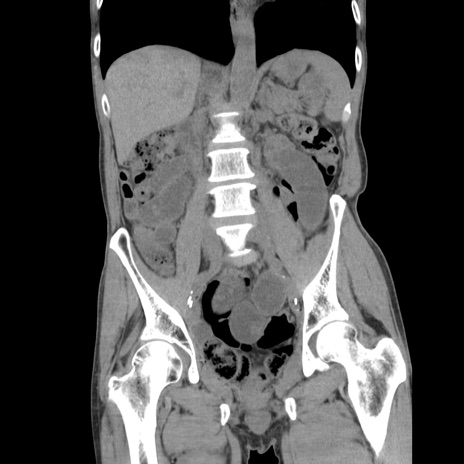

症例11(冠状断像)

【症例】 60歳代男性

【主訴】 下腹部痛

【現病歴】 本日夜中より下腹部痛の症状認め、受診。

【既往歴】 膀胱癌(膀胱全摘+尿管皮膚瘻術) 、胃癌術後

【身体所見】 BT 35.3℃、PR 58/min、BP 136/98mHg、腹部平坦、軟、腸蠕動音±、ストマ留置あり、左上腹部~正中部に圧痛あり、反跳痛なし。

【データ】WBC 5100、CRP0.01